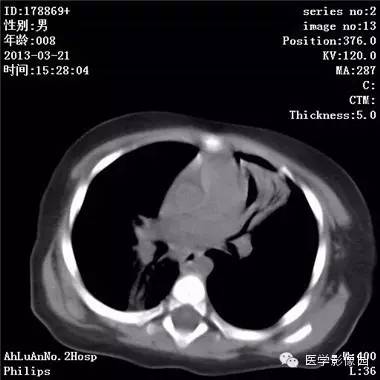

【病例】支气管异物1例CT影像表现

患儿男,8个月,呛咳,发热一周。实验室检查白细胞及中性粒细胞增高。

两肺肺纹理增多、增粗,右肺可见斑片状、片絮状模糊影,边界欠清;左肺上叶见楔形高密度影,内可见支气管征,尖端指向肺门;左肺下叶肺野透亮度增强;另见左肺主支气管内可见块状软组织密度影。

支气管异物(花生米)伴两肺炎症(追问病史,患儿奶奶层于一周前喂食患儿花生米,当时疑似“呛进去”,后来见好了也就没留意)。